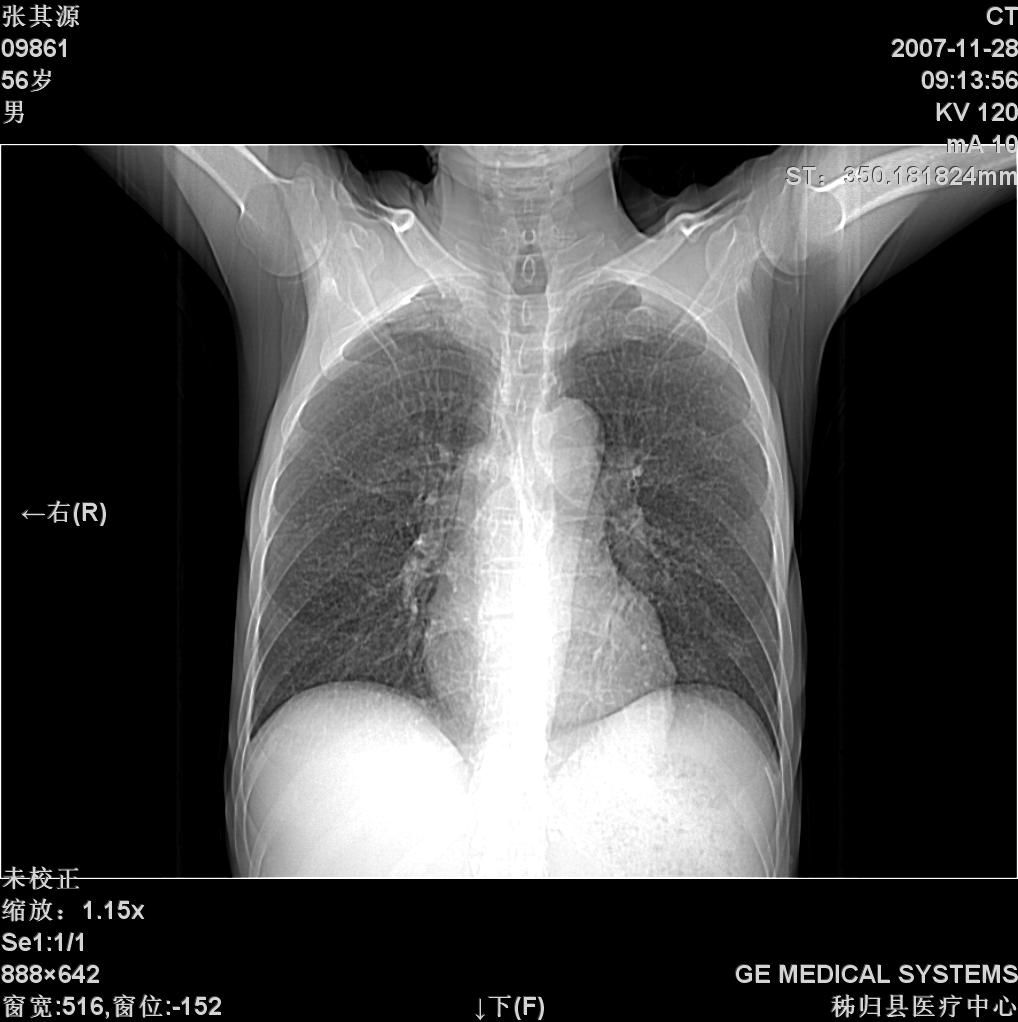

患者因阻塞性黄疸入院,发病前10天持续中等程度发烧.术前检查发现两肺弥漫性病变,请各位大虾会诊,除了考虑急性血源性肺结核外,还有其他什么疾病可能.

补充一下,该患者没有与尘肺相关职业史。请大家帮忙会诊一下,外科医生打算为其做胆总管肿瘤做手术的,现在在等我们的结果。谢谢各位了。

双肺多发粟粒样病灶,右肺胸膜下结节样病灶,气管前腔静脉后及隆突下均见肿大淋巴结,结合胆道肿瘤病史首先考虑转移。另外心影密度略低,时间格显示,是否有贫血?查明白再手术吧!